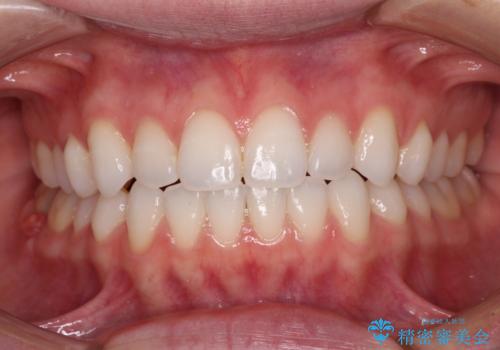

上下前歯が接触しない オープンバイトをインビザラインで改善

上下の奥歯を圧下させるようにすることで、前歯を接触させるように計画しました。

上下の隙間に舌が入り込むことがオープンバイトの原因であったため、舌の筋肉のトレーニングも並行して行い、後戻りの抑制を図りました。